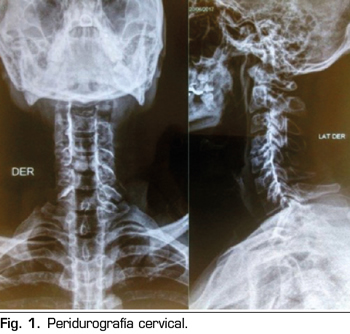

Pasa a recuperación donde hubo regresión completa del bloqueo cervical; el paciente se mantiene estable y con evolución favorable; fue evaluado por el servicio de terapia del dolor, donde se decide observar la permeabilidad del catéter, utilizando una sustancia de contraste iodado no iónico 3 cc, evidenciando en la imagen de “Peridurografía cervical” la difusión del contraste a ambos lados del espacio epidural (Figura 1), procediendo a continuar la analgesia en el postoperatorio a través del catéter epidural cervical con morfina 5 mg, bupivacaína 0,05 % y cloruro de sodio a 0,9 % 90 cc a través de bomba elastómerica a un flujo de 0,5 cc/hora durante 5 días. Se realizó el seguimiento durante la hospitalización, con controles en el postoperatorio inmediato y al primer día, teniendo un EVA 0/10, en estas dos evaluaciones, sin presentar ninguna complicación; fue dado de alta el 2.º día del postoperatorio con la infusión por bomba elastómerica, con un EVA 0/10, reevaluándose al 5.º día del postoperatorio por consultorio externo de terapia del dolor, presentando un EVA 0/10 y sin complicaciones desde el alta (Figura 2), procediendo al retiro del catéter epidural.